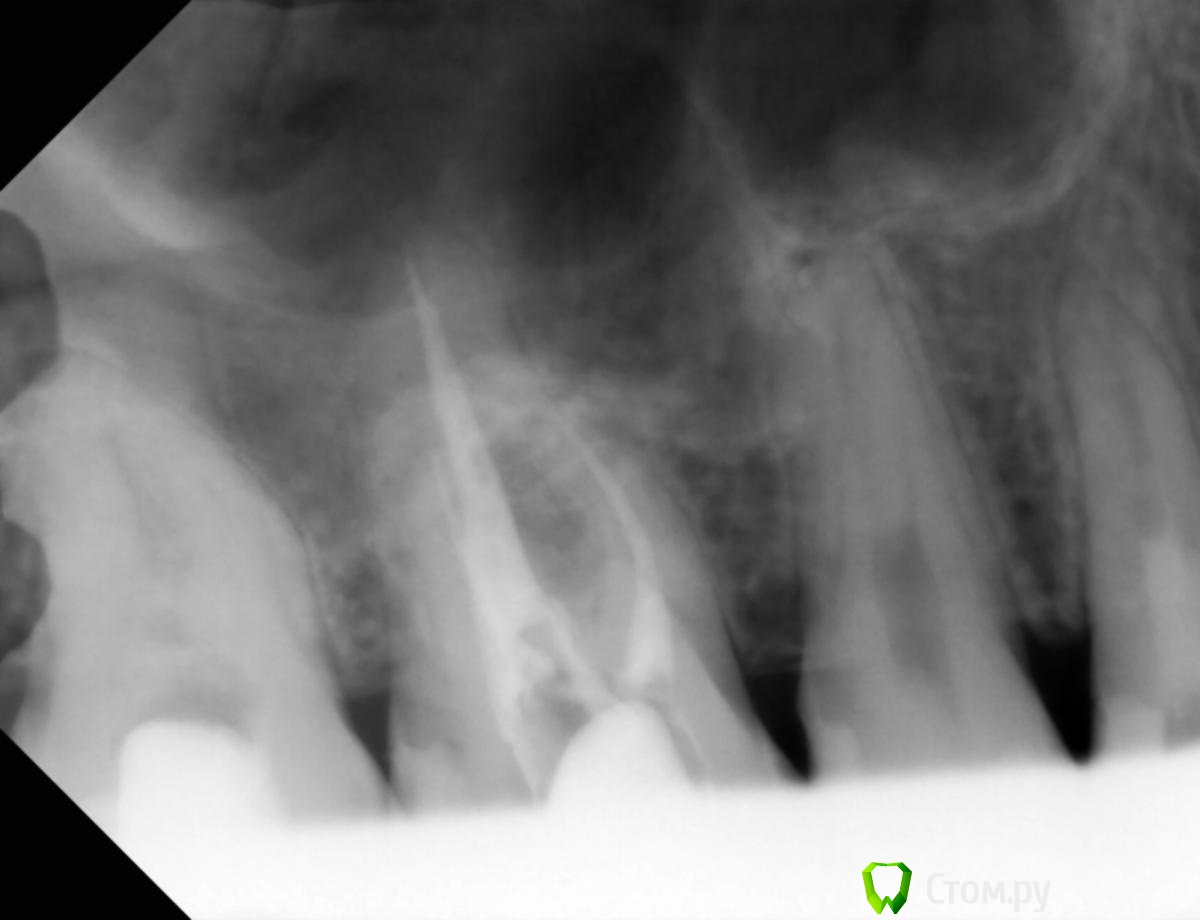

Юлия Арт Опубликовано 12 марта, 2014 Поделиться Опубликовано 12 марта, 2014 здравствуйте! мне всего 26 лет, ситуация с зубами у меня критическая, уже 2 удалены из-за больших кист под ними, сейчас болят сильно три коренных зуба наверху 8-6-4 , болели обычно когда ела, старалась избегать контакта с ними, языком пробовала зубы-стреляло сильно. Врач посмотрел снимки, сказал что пломбы очень глубокие, доходят до нервов, выход только удалять нервы. Пару дней назад начали удаление нервов в 3-х зубах, боль пульсирующая прошла, на холодное не болит, но докасаться до зубов невозможно, болит так же! есть на них не могу, если по зубам постучать-небольно,но если немного из стороны в сторону надавить на некоторые участки этих зубов - болит сильно! Уже не знаю что делать...врач говорит что надо подождать, но чего ждать когда мне ясно что удаление нервов не помогло. Уже думаю, может, они поломаны...есть снимок до удаления нервов пожалуйста, помогите советом что делать и что может быть с моими зубами Ссылка на комментарий

Юлия Арт Опубликовано 12 марта, 2014 Автор Поделиться Опубликовано 12 марта, 2014 снимок сделан в прошлом году, другого пока нет. нижняя 6-как и верхняя 5-ка удалены так как кисты под ними были.3 зуба с нервами за 2 дня депульпировали так как болело так что обезболивающее не брало... уже сомневаюсь что надо было это делать, хотя каналы кровили во всех зубах-пульпит был долгое время Ссылка на комментарий

Юлия Арт Опубликовано 13 марта, 2014 Автор Поделиться Опубликовано 13 марта, 2014 вот фото, панорамный сделали сегодня (вторая кист куда-то делась у верхней 5-ки, вырывать зуб не стали),троица с депульпцией болит и ноет сильно, есть на них не могу Ссылка на комментарий

anvladd Опубликовано 13 марта, 2014 Поделиться Опубликовано 13 марта, 2014 17 зуб похоже проблемный уж слишком пломба глубоко. Ссылка на комментарий

Л Ю С Я Опубликовано 13 марта, 2014 Поделиться Опубликовано 13 марта, 2014 1.4 перелечивать, разобраться с 1.7 и 1.5, возможно и 1.6 проблемный Ссылка на комментарий

anvladd Опубликовано 13 марта, 2014 Поделиться Опубликовано 13 марта, 2014 Нерв удалили в 16 а вот 17 судя по снимку под подозрением. И как писала доктор выше 14 перелечивать каналы. Ссылка на комментарий

Юлия Арт Опубликовано 13 марта, 2014 Автор Поделиться Опубликовано 13 марта, 2014 (изменено) уважаемые, уже третий день после начала депульпации 7, 6(завершено) и 4-го верхних болит вся цека и все зубы 7-6-5-4...есть на них не могу, такое ощущение что их распирает изнутри, если стучать по ним-небольно, но есть неокторые места куда если пища попадает или пальцем надавить - стреляет больно! через 2 недели только приём у врача на завершение депульпации... а я ждать не смогу, отнимается левая верхняя сторона. судя по фото, что там может быть? или нервы в зубах или , может, они поломаны или десна воспалены? воможности КТ сделать пока нет Изменено 13 марта, 2014 пользователем Юлия Арт Ссылка на комментарий

anvladd Опубликовано 13 марта, 2014 Поделиться Опубликовано 13 марта, 2014 уважаемые, уже третий день после начала депульпации 7, 6(завершено) и 4-го верхних болит вся цека и все зубы 7-6-5-4...есть на них не могу, такое ощущение что их распирает изнутри, если стучать по ним-небольно, но есть неокторые места куда если пища попадает или пальцем надавить - стреляет больно! через 2 недели только приём у врача на завершение депульпации... а я ждать не смогу, отнимается левая верхняя сторона. судя по фото, что там может быть? или нервы в зубах или , может, они поломаны или десна воспалены? воможности КТ сделать пока неттак потому и болит что,как я понимаю,не завершена депульпация 7 и 4 зубов. Вы вложили снимок до или после депульпации, напишите. 1 Ссылка на комментарий

Юлия Арт Опубликовано 14 марта, 2014 Автор Поделиться Опубликовано 14 марта, 2014 так потому и болит что,как я понимаю,не завершена депульпация 7 и 4 зубов. Вы вложили снимок до или после депульпации, напишите.всё верно понимаете, у 6-го каналы вроде почистили, хотя я тут начиталась что их там 4-ре, врач нашёл только 3. 6-й тоже болит сильно, они вообще все с 7-го по 4-й дружно ноют и стреляют. скорее всего там не просто пульпит был, но и периодонтит судя по моим симптомам Ссылка на комментарий

anvladd Опубликовано 14 марта, 2014 Поделиться Опубликовано 14 марта, 2014 тогда долечивать 7,4 и перелечивать 6,искать 4й канал. удачи. Ссылка на комментарий